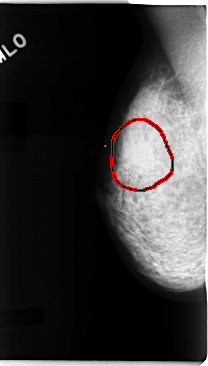

FILE: C_0092_1.RIGHT_MLO.OVERLAY

TOTAL_ABNORMALITIES 1

ABNORMALITY 1

LESION_TYPE CALCIFICATION TYPE PLEOMORPHIC DISTRIBUTION CLUSTERED

LESION_TYPE MASS SHAPE OVAL MARGINS ILL_DEFINED

ASSESSMENT 5

SUBTLETY 5

PATHOLOGY MALIGNANT

TOTAL_OUTLINES 1

BOUNDARY